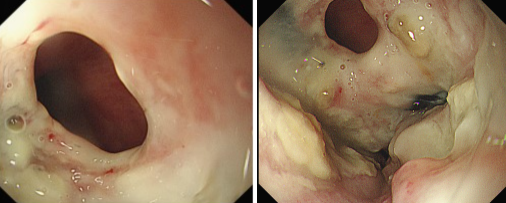

品質(zhì)國文 | 重獲進(jìn)食希望——內(nèi)鏡下食管覆膜支架植入手術(shù)

張大爺近期突然遭遇進(jìn)食困難,還頻繁出現(xiàn)進(jìn)食嗆咳的狀況。緊急檢查后,確診為食管惡性腫瘤,同時并發(fā)食管氣管瘺,而且因食物誤吸引發(fā)了肺部感染。由于瘺口的存在,食物不斷進(jìn)入氣道,致使嗆咳加劇、感染惡化,這不僅嚴(yán)重降低了張大爺?shù)纳钯|(zhì)量,更對其生命構(gòu)成了極大威脅。 閱讀量:1930